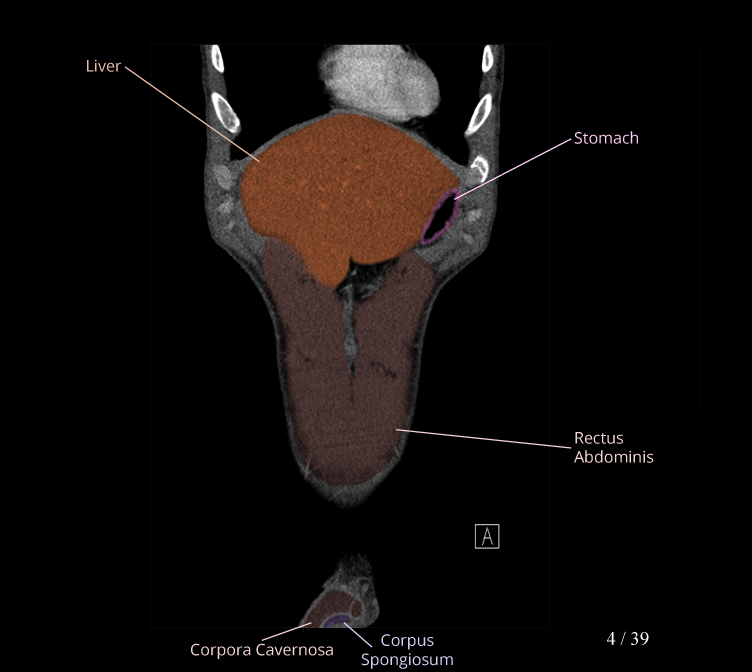

Body

Covers abdominal CT anatomy.